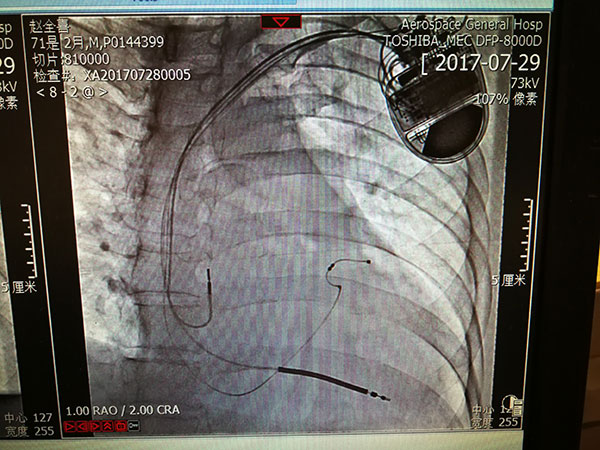

7月29日,總醫(yī)院的一位住院患者突發(fā)惡性心律失常,心率達(dá)到263次/分,危在旦夕??傖t(yī)院啟動應(yīng)急預(yù)案,開啟綠色通道,成立了專家小組,由戴天然院長親自指導(dǎo),心內(nèi)科李茂榮主任和甘豐副主任具體負(fù)責(zé)。為搶救患者生命,專家小組在幾經(jīng)討論,充分和家屬溝通后,果斷決定對患者采取植入式再同步心律轉(zhuǎn)復(fù)除顫器的手術(shù)。隨后總醫(yī)院多科室迅速聯(lián)動,在最短時間內(nèi)為患者安排了手術(shù),克服重重困難為患者成功植入除顫器,現(xiàn)在患者情況恢復(fù)良好,已準(zhǔn)備出院。